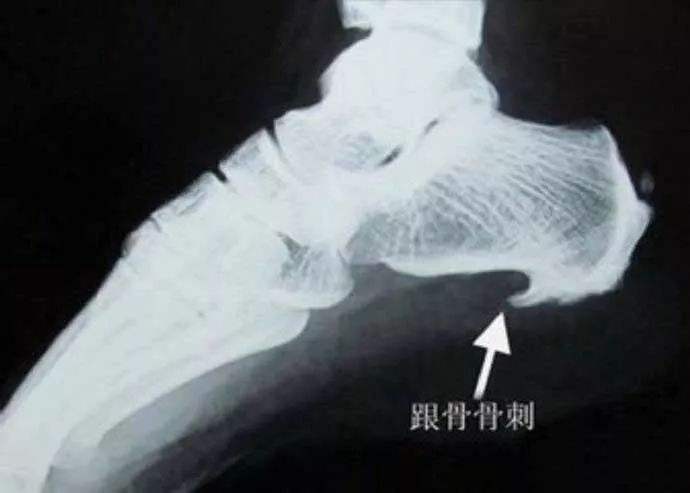

所以我们可以看到,骨刺生长的地方,主要是负重大、使用频繁的重要关节,比如颈椎、腰椎、膝盖、脚跟等等。

骨质增生是机体恢复新的平衡的一种自我保护机制。当新的平衡建立,脊柱或关节重新恢复到稳定状态时,骨质增生自然会停止。这时候疼痛等症状反而消除了!比如像足跟的骨刺在骨刺没出来之前是最疼的,骨刺长好稳定了反而不疼了,这就是人体靠自己的修复能力调节的结果。